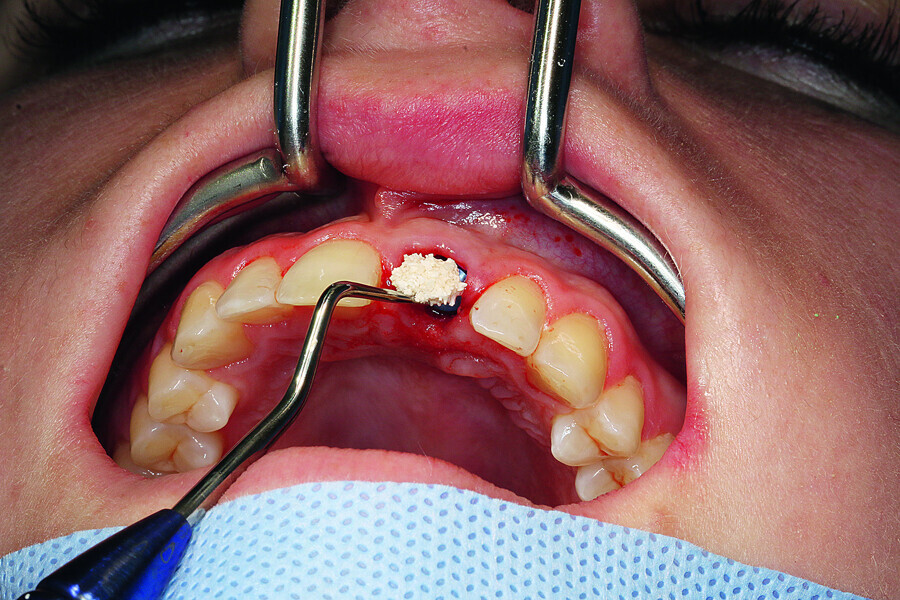

Fig. 10: Intra-op CEREC scanning with a ScanPost.